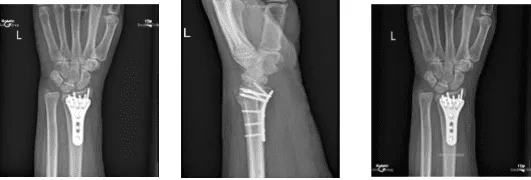

She is here for her postoperative visit with x-rays. Her pain is well controlled. She has been opening her splint and wrapping back since surgery. She has stiffness in her fingers .X rays were reviewed and discussed; Status post ORIF of a comminuted intra-articular fracture of the distal radius, without complete fracture healing.

X-ray Left Wrist Minimum 3 views